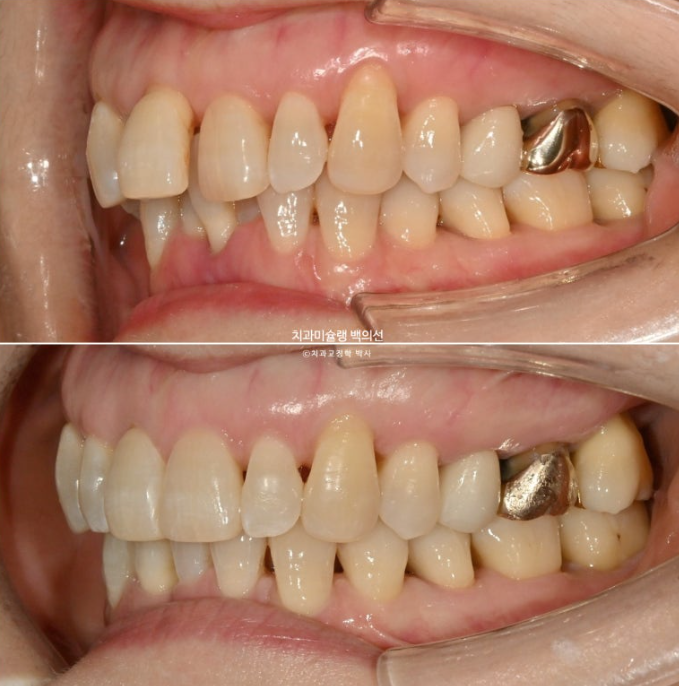

이제 전 후 비교 보겠습니다.

24.09~25.09

앞니가 깊게 물리는 과개교합이 개선되었습니다.

특히 뿌리가 보일 정도로 솟아내려와있던 파란 화살표 앞니가 건강하게 제 위치로 함입이 되고 노출된 뿌리 부분이 다시 잇몸속으로 안정적으로 들어갔습니다.

약해진 잇몸으로 인해 솟아나온 앞니 때문에 편하게 안 다물리던 입술이 비로소 편하게 다물리는 것 역시 기능적으로 큰 개선입니다.